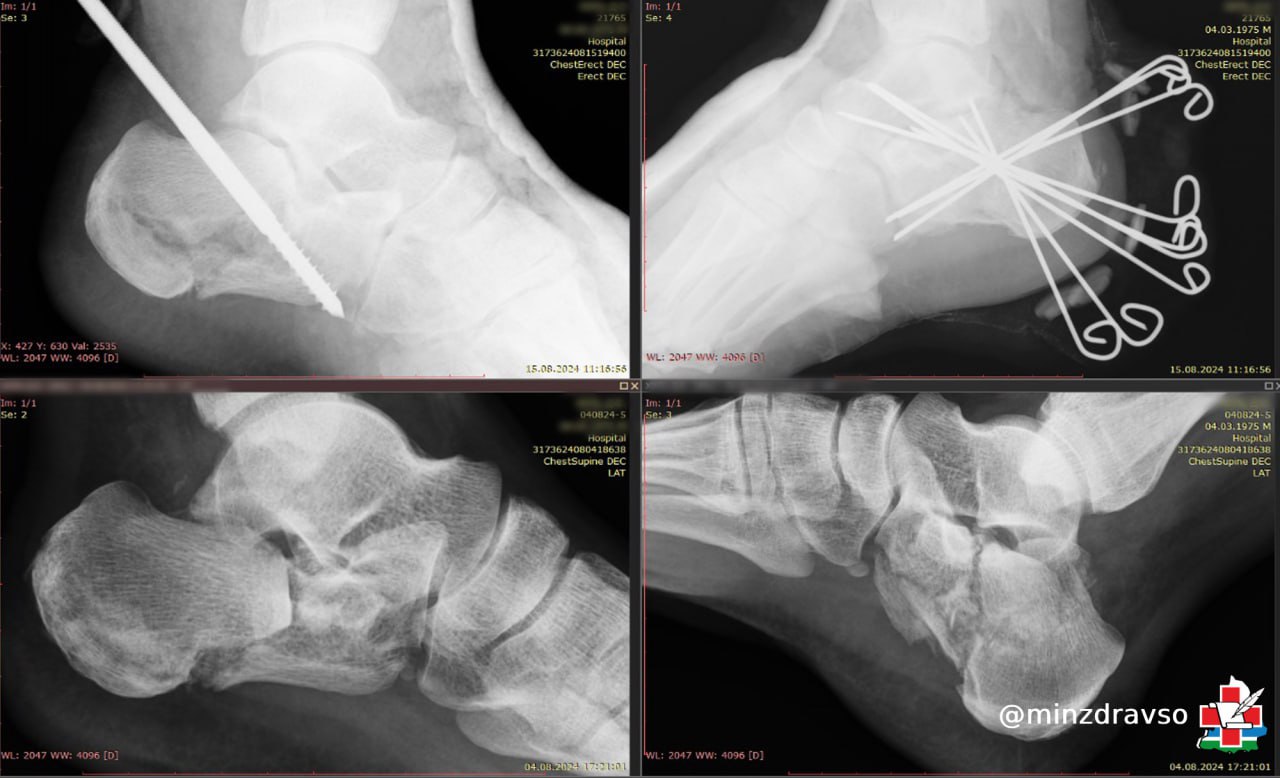

Режевлянин Дмитрий получил травму, упав в конце лета с лестницы высотой около трёх метров. Приземление было крайне неудачным — у мужчины диагностировали внутрисуставной оскольчатый перелом правой и левой пяточной костей. Травматологи Центральной городской клинической больницы №24 Екатеринбурга выполнили операцию по закрытому остеосинтезу спицами, что позволило восстановить целостность костей без осложнений. После этого мультидисциплинарной команде Областной специализированной больницы медицинской реабилитации «Липовка» предстояло помочь уральцу заново встать на ноги.